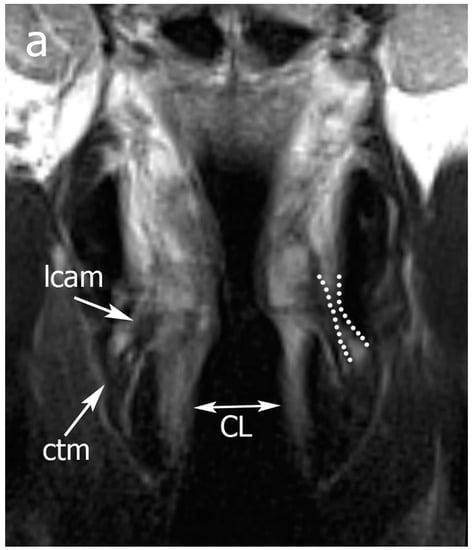

Figure 3.

Example of Pattern B. From top to the bottom: (a) TSE-T2 on coronal plane; (b) TSE-T2 on axial plane. A right glottic tumor that does not invade the posterior laryngeal compartment (PLC) is seen. In (a), normal signals of lateral cricoarytenoid and cricothyroid muscles are displayed, the cricoid lamina is normal, and an inferior paraglottic space (PGS) is indicated by dotted lines. In (b), expansion of the right PLC (dotted black lines) is seen. A high T2 signal in the PLC is consistent with an intense edema that hampers crico-arytenoid unit (CAU) functionality. Legend: Ac, arytenoid cartilages; CL, cricoid lamina; ctm, cricothyroid muscle; e, edema; lcam, lateral cricoarytenoid muscle.